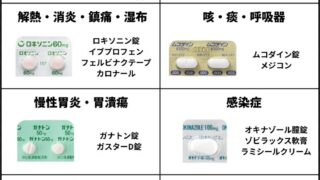

副作用は稀ですが、胃もたれや下痢が起きる場合があります。アレルギー(魚・牛由来)のある方は避け、腎臓病患者は高タンパクのため医師に相談を。薬との相互作用は報告されていませんが、NSAIDs使用中は注意。過剰摂取は逆効果になる可能性があります。

品質の悪い製品は効果が低いので、第三者機関検査済みを確認。効果を感じない場合は用量調整や中断を検討してください。サプリは補助療法で、運動・減量が基本です。

| NSAID薬 | 高(痛み止め) | 1,000円〜 | 高(胃痛) | 低 |